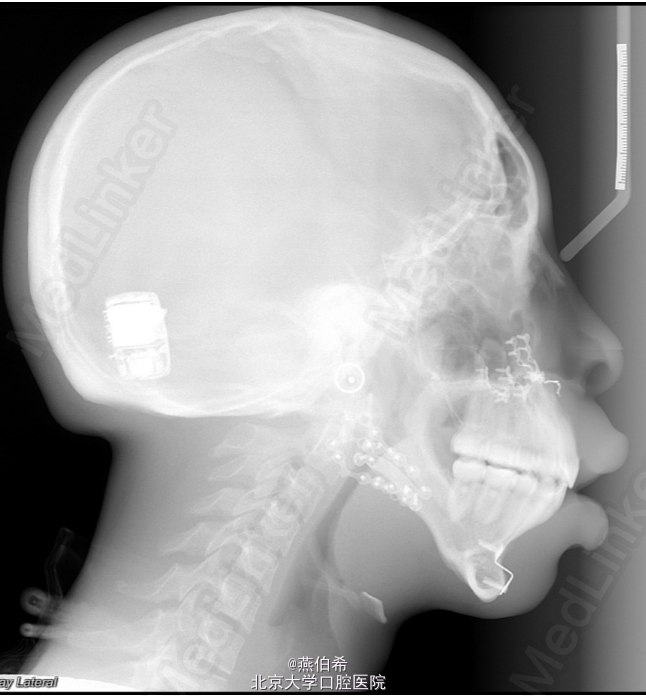

Treacher Collins综合征 扩弓解决宽度不调,拔4个4矫正牙量骨量不调, 后行口外反L行截骨术矫正颌骨问题

术后效果良好。 Treacher Collins 综合征,下颌-面骨发育不全 患病率为每50,000活婴儿中有1个 其表现为颧弓发育不全(81%),小颌畸形(78%)以及由于外耳道闭锁引起的外耳形态异常,同时可能听小骨确实引起的传导性耳聋。 口腔内的表现为高腭穹窿,唇裂,腭裂,牙釉质发育不良,及骨骼导致的前牙开牙合。前磨牙不萌出和上磨牙异位萌出也很常见。 (AJODO,November 2014 Vol 146 Issue 5)